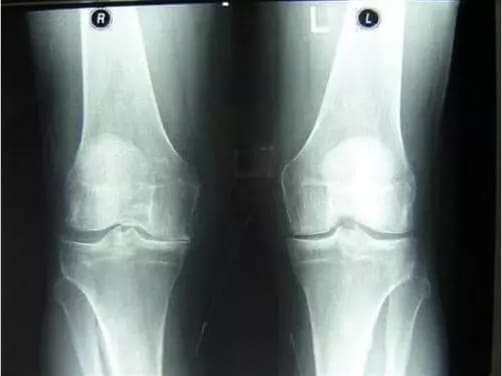

Вы только посмотрите на рентген суставов до и после использования «Сусталита»:

Женщина. 54 года. Ее сустав полностью восстановился.

Продолжительность курса: 2,5 месяца.

Изменения в суставе бедра у 44-летнего мужчины.

Острые боли, которые его мучили в течение 2-х лет, исчезли.